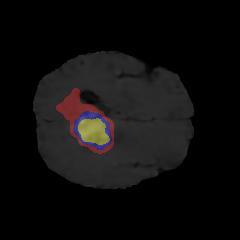

Brain tumor segmentation. Segmenting tumors in brain is challenging due to the high variance in appearance and shape of the tumors [28]. We use a subset of the 2017 Brain Tumour Image Segmentation (BraTS) dataset [29, 26]. It contains multi-parametric 3D MRI scans. The segmentation masks include (possibly overlapping) three classes of tumor. The 3D scans are split into 2D image slices, and only images that contain at least one tumor class are retained. Figure 7 shows three MSGNet generated samples as well as the corresponding masks. Since MSGNet adheres to the underlying relationships between various classes, we see that the generated images and the masks for different tumor classes are in line with the images and masks from the training set. In general, MSGNet rarely generated erroneous samples; we found roughly one sample per 3000 generations that could be rejected. Similar to the malaria experiment, we observed an improvement of 3.1% () in -score on the validation set.

A subset of the BrATS dataset was used. We used the images accompanied by segmentation layouts from the FLAIR and T1Gd modes. The segmentation layouts showed the sub-regions for three different classes: GD-enhancing tumor, the peritumoral edema, and the necrotic and non-enhancing tumor core. The brain and the background were treated as an additional class. We refer to [32] for further details. For the two modes, the background has been modelled using two different classes. We only considered half of the 155 slices, i.e., we took only the even-numbered slices and out of those we discarded the slices that did not include one of the previously mentioned tumor-classes in order to create a more balanced dataset. This resulted in 20,000 images that were further augmented with 6,000 MSGNet generated images. Example generations of the masks as well as the images are shown in Figure 12.